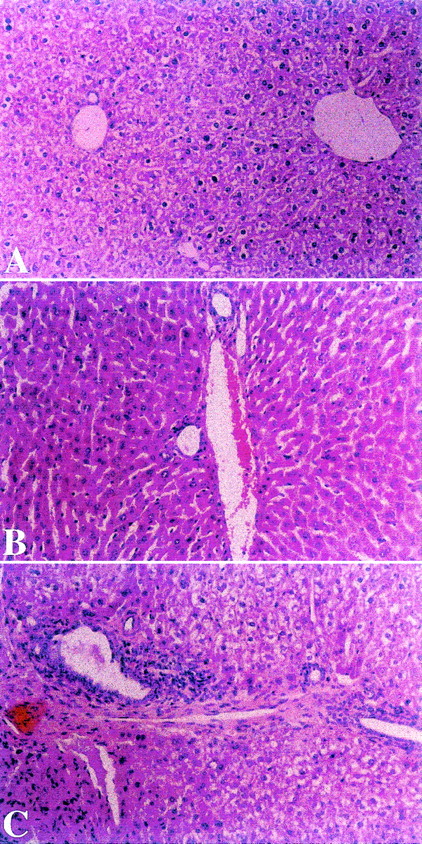

Liver biopsies were performed on all splenocyte recipients from all groups 52 days after transplantation. Mice in experimental group A, fed after transplantation with homogenates of splenocytes derived from recipient strain BALB/c mice, showed mild degrees of portal inflammation, lymphocyte infiltration, and/or disruption of intrahepatic bile ducts (Figure 3A). In contrast, biopsy specimens from control nontolerant recipients in groups B and C, fed after transplantation with homogenates prepared from B10.D2 mouse splenocytes or BSA, respectively, showed portal inflammation and bile duct destruction (Figure 3B and C). With the use of the standardized score grading for liver and bile duct involvement in cGVHD, group A recipients achieved a sum score of 1.90 ± 0.42, compared with 2.3 ± 0.41 and 2.58 ± 0.38 in control groups B and C (n = 6, group A vs B, P < .005; group A vs C,P < .004).

Liver biopsies were performed on splenocyte recipients 52 days after transplantation. Mice in experimental group A, fed after transplantation with homogenates of splenocytes derived from recipient strain BALB/c mice showed mild degree of portal inflammation (Panel A). In contrast, biopsies from control nontolerant recipients in groups B and C, fed after transplantation with homogenates prepared from B10.D2 mouse splenocytes or BSA, respectively, showed portal and bile duct inflammation (Panels B and C). (HαE, original magnification ×40.)